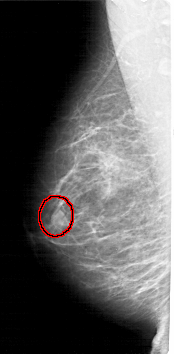

A_1982_1.LEFT_CC

LEFT_CC LINES 4921 PIXELS_PER_LINE 2461 BITS_PER_PIXEL 12 RESOLUTION 43.5 OVERLAY

FILE: A_1982_1.LEFT_CC.OVERLAY

TOTAL_ABNORMALITIES 1

ABNORMALITY 1

LESION_TYPE MASS SHAPE OVAL MARGINS ILL_DEFINED

ASSESSMENT 4

SUBTLETY 3

PATHOLOGY BENIGN

TOTAL_OUTLINES 1

BOUNDARY